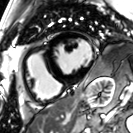

感染性心肌疾病—心肌炎合并心肌缺血

心脏成像 --- 压缩感知电影

自由呼吸,无需屏气

捕获全心动周期数据

临床价值

成像速度和图像质量同时提升

定量数据更精准

心脏MR适用人群更广